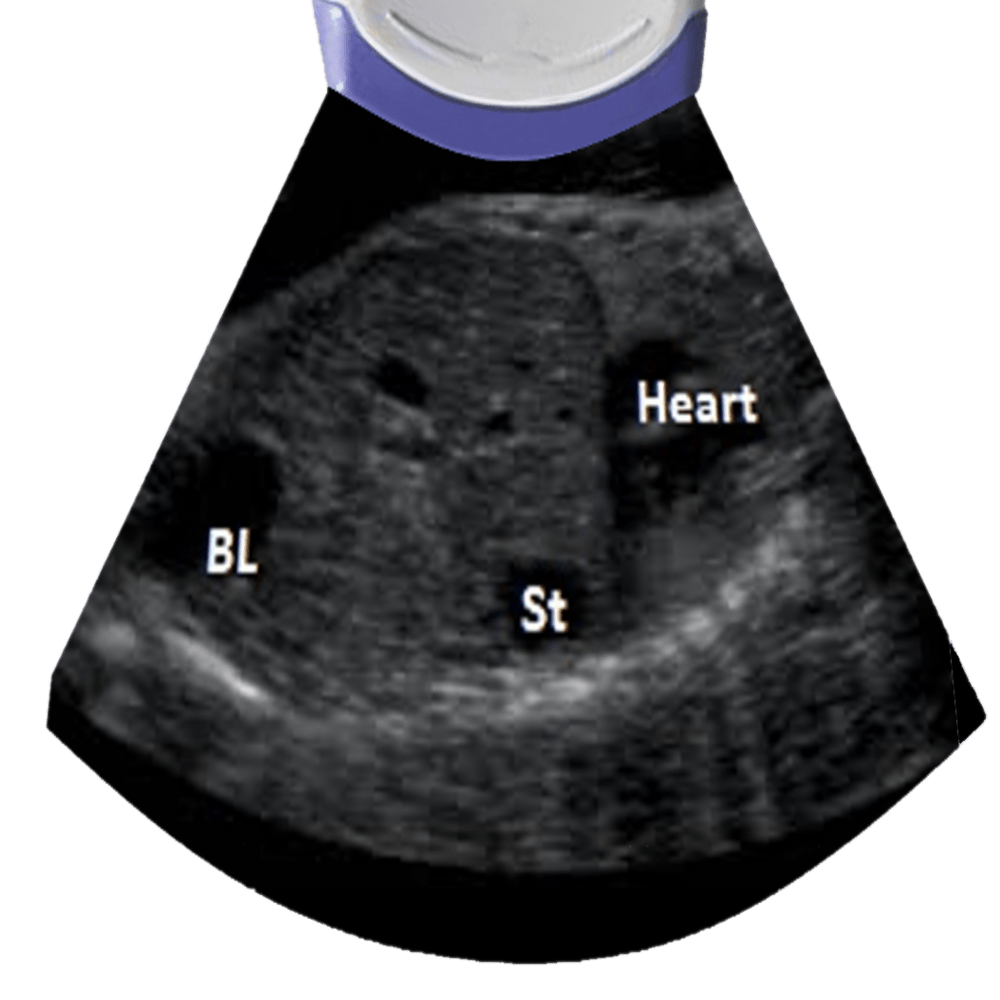

Heart, stomach and bladder view can rule situs inversus.

Heart size relation to chest (hear takes up 1/3 of the chest with the apex pointing to the left).

Four chamber view, also asses the lung parenchyma.